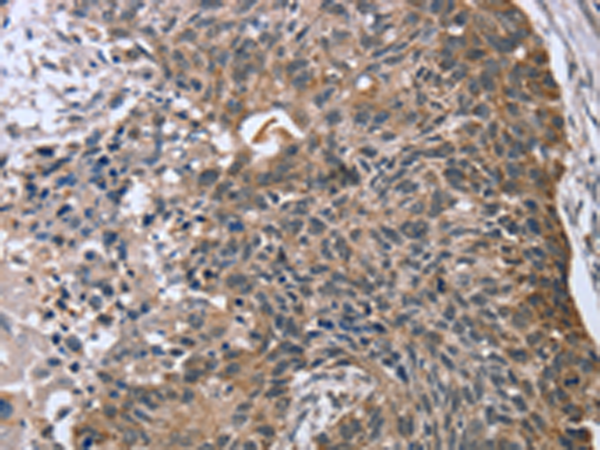

分类: 科研抗体货号: P01709别名: HRC1; HRAS1; C11orf13应用: WB,IHC反应种属: Human